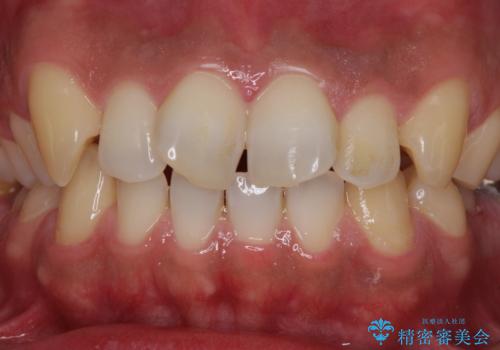

- 前歯が捻れており出っ歯であることを気にして来院された患者様です。

虫歯がほとんどなく、前歯以外にも歯列に問題があったため、歯列矯正を第一選択として強く勧めました。

しかし、時間をかけることは避けたいという強い要望があったため、セラミッククラウンによる補綴治療を行うこととしました。

補綴治療に先立ち、歯の形態を修正する必要があったため、残念ではありますが根管治療を行うこととしました。